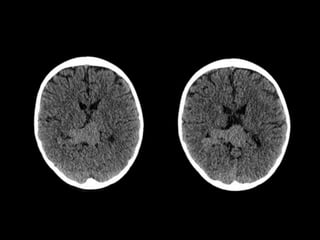

TC CEREBRAL SIMPLE

08-06-2023.

TC SIMPLE DE CRANEO

08/06/2023

Lesión ocupante de espacio extraaxial

supratentorial a nivel de cisterna cuadrigeminal.

CONCLUSIONES:

ESTUDIOS REALIZADOS: TC CEREBRALSIMPLE 08-06-2023. RNM CEREBRAL 20-06-2023.

TC SIMPLE DECRANEO 08/06/2023

Lesión ocupante deespacio extraaxial supratentorial a nivel de cisterna cuadrigeminal. CONCLUSIONES: